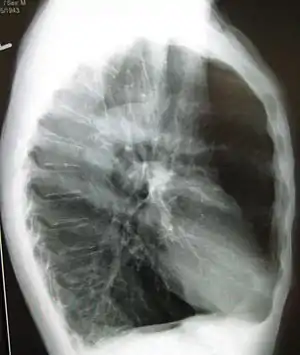

| تصویر رادیولوژی از یک ریه دچار آمفیزم. به دیافراگم مسطح و فاقد خمیدگی عادی توجه کنید. | |